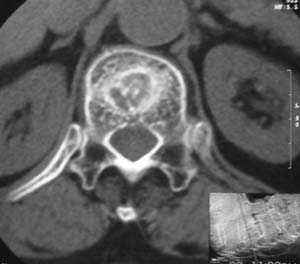

患者,女,72岁,胸背部疼痛3月余,无明显外伤史。曾应用局部封闭、非甾体类止痛药治疗效果不明显,近来疼痛缓解频感背困,平卧缓解,近日行ct检查发现胸12椎体病变,烦请同道发表意见,诊断什么?有何治疗经验!谢谢!!!

标绘图示:第十二胸椎级第一腰椎椎体楔形改变。ct扫描示:第十二胸椎椎体骨质结构紊乱,并可见一囊状低密度影,边缘可见硬化,椎体皮质完整。

考虑:第十二胸椎陈旧性骨折、许莫氏结节。